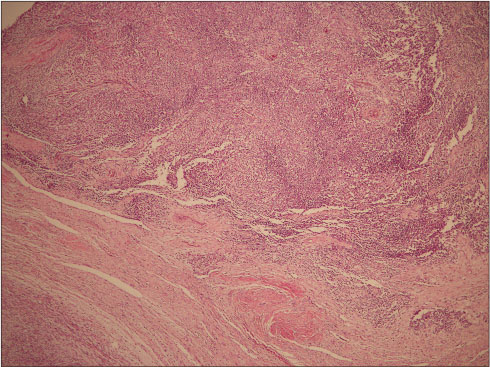

A 34-year-old female presented to us with increased bleeding per vaginum during her menstrual cycles associated with severe dysmenorrhea since 6 months. She was para 2, live 2, abortion 1. Her previous cycles were normal. She underwent endometrial biopsy outside 3 months back, and the histopathology reported as nonsecretory endometrium. She had failed medical management for AUB. On examination, her vitals were stable; general and systemic examination was within normal limits. Per abdomen examination revealed a soft abdomen with no mass or ascites. Speculum examination showed a healthy cervix and liquid-based cytology was reported as normal. On bimanual pelvic examination, uterus was anteverted, mobile, 12?14 weeks size. Ultrasound with Doppler flows revealed an anteverted bulky uterus of 10.2 cm ? 5.6 cm ? 4.1 cm with 14 mm ? 13 mm hypoechoic area suggestive of fibroid in the posterior wall of uterus not distorting the endometrial cavity. Endometrial thickness was 4 mm. Bilateral ovaries were normal. Doppler flows were within normal limits suggestive of benign lesion. The patient and her family were counseled and given various treatment options available for the management of her problem. They insisted on hysterectomy as a permanent treatment by laparoscopic approach. Patient was taken up for D/C followed by frozen section of endometrial curetting, total laparoscopic hysterectomy with bilateral salpingectomy with ovarian conservation. The frozen section revealed a benign endometrium. Intraoperative findings were a globular uterus, 14-week size with multiple seedling fibroids. On cut section of the specimen, cavity was regular. Myohyperplasia was present with multiple intramural small seedling fibroids with a single 2 cm ? 2 cm fibroid on the left posterior wall. Patient was discharged in a stable condition. Surprisingly, the histopathology report was suggestive of a single submucosal nodular lesion of 1.2 cm seen in the myometrium with infiltrative and focally permeative margins into myometrium [Figure 1]. Tumor showed discrete highly cellular high-grade round cell areas and hypocellular spindle cell component. The round cells had oval vesicular nuclei with irregular contours and focally prominent nucleoli with a moderate amount of eosinophilic cytoplasm. Hypocellular component showed fibromyxoid background with large bizarre cells with no increase in mitosis. Lymphovascular invasion was equivocal. On immunohistochemistry staining, the high-grade component was positive for Cyclin D1 and negative for CD10 [Figure 2] and [3]. Ki67 proliferation index was 15%?18%. The low-grade component was positive for CD10 and negative for Cyclin D1. Ki67 proliferation index was 1%?2%. HMB45 was negative for both the components.

|?Figure. 1? Low-power view showing intramyometrial cellular malignant neoplasm (H and E, ?40)